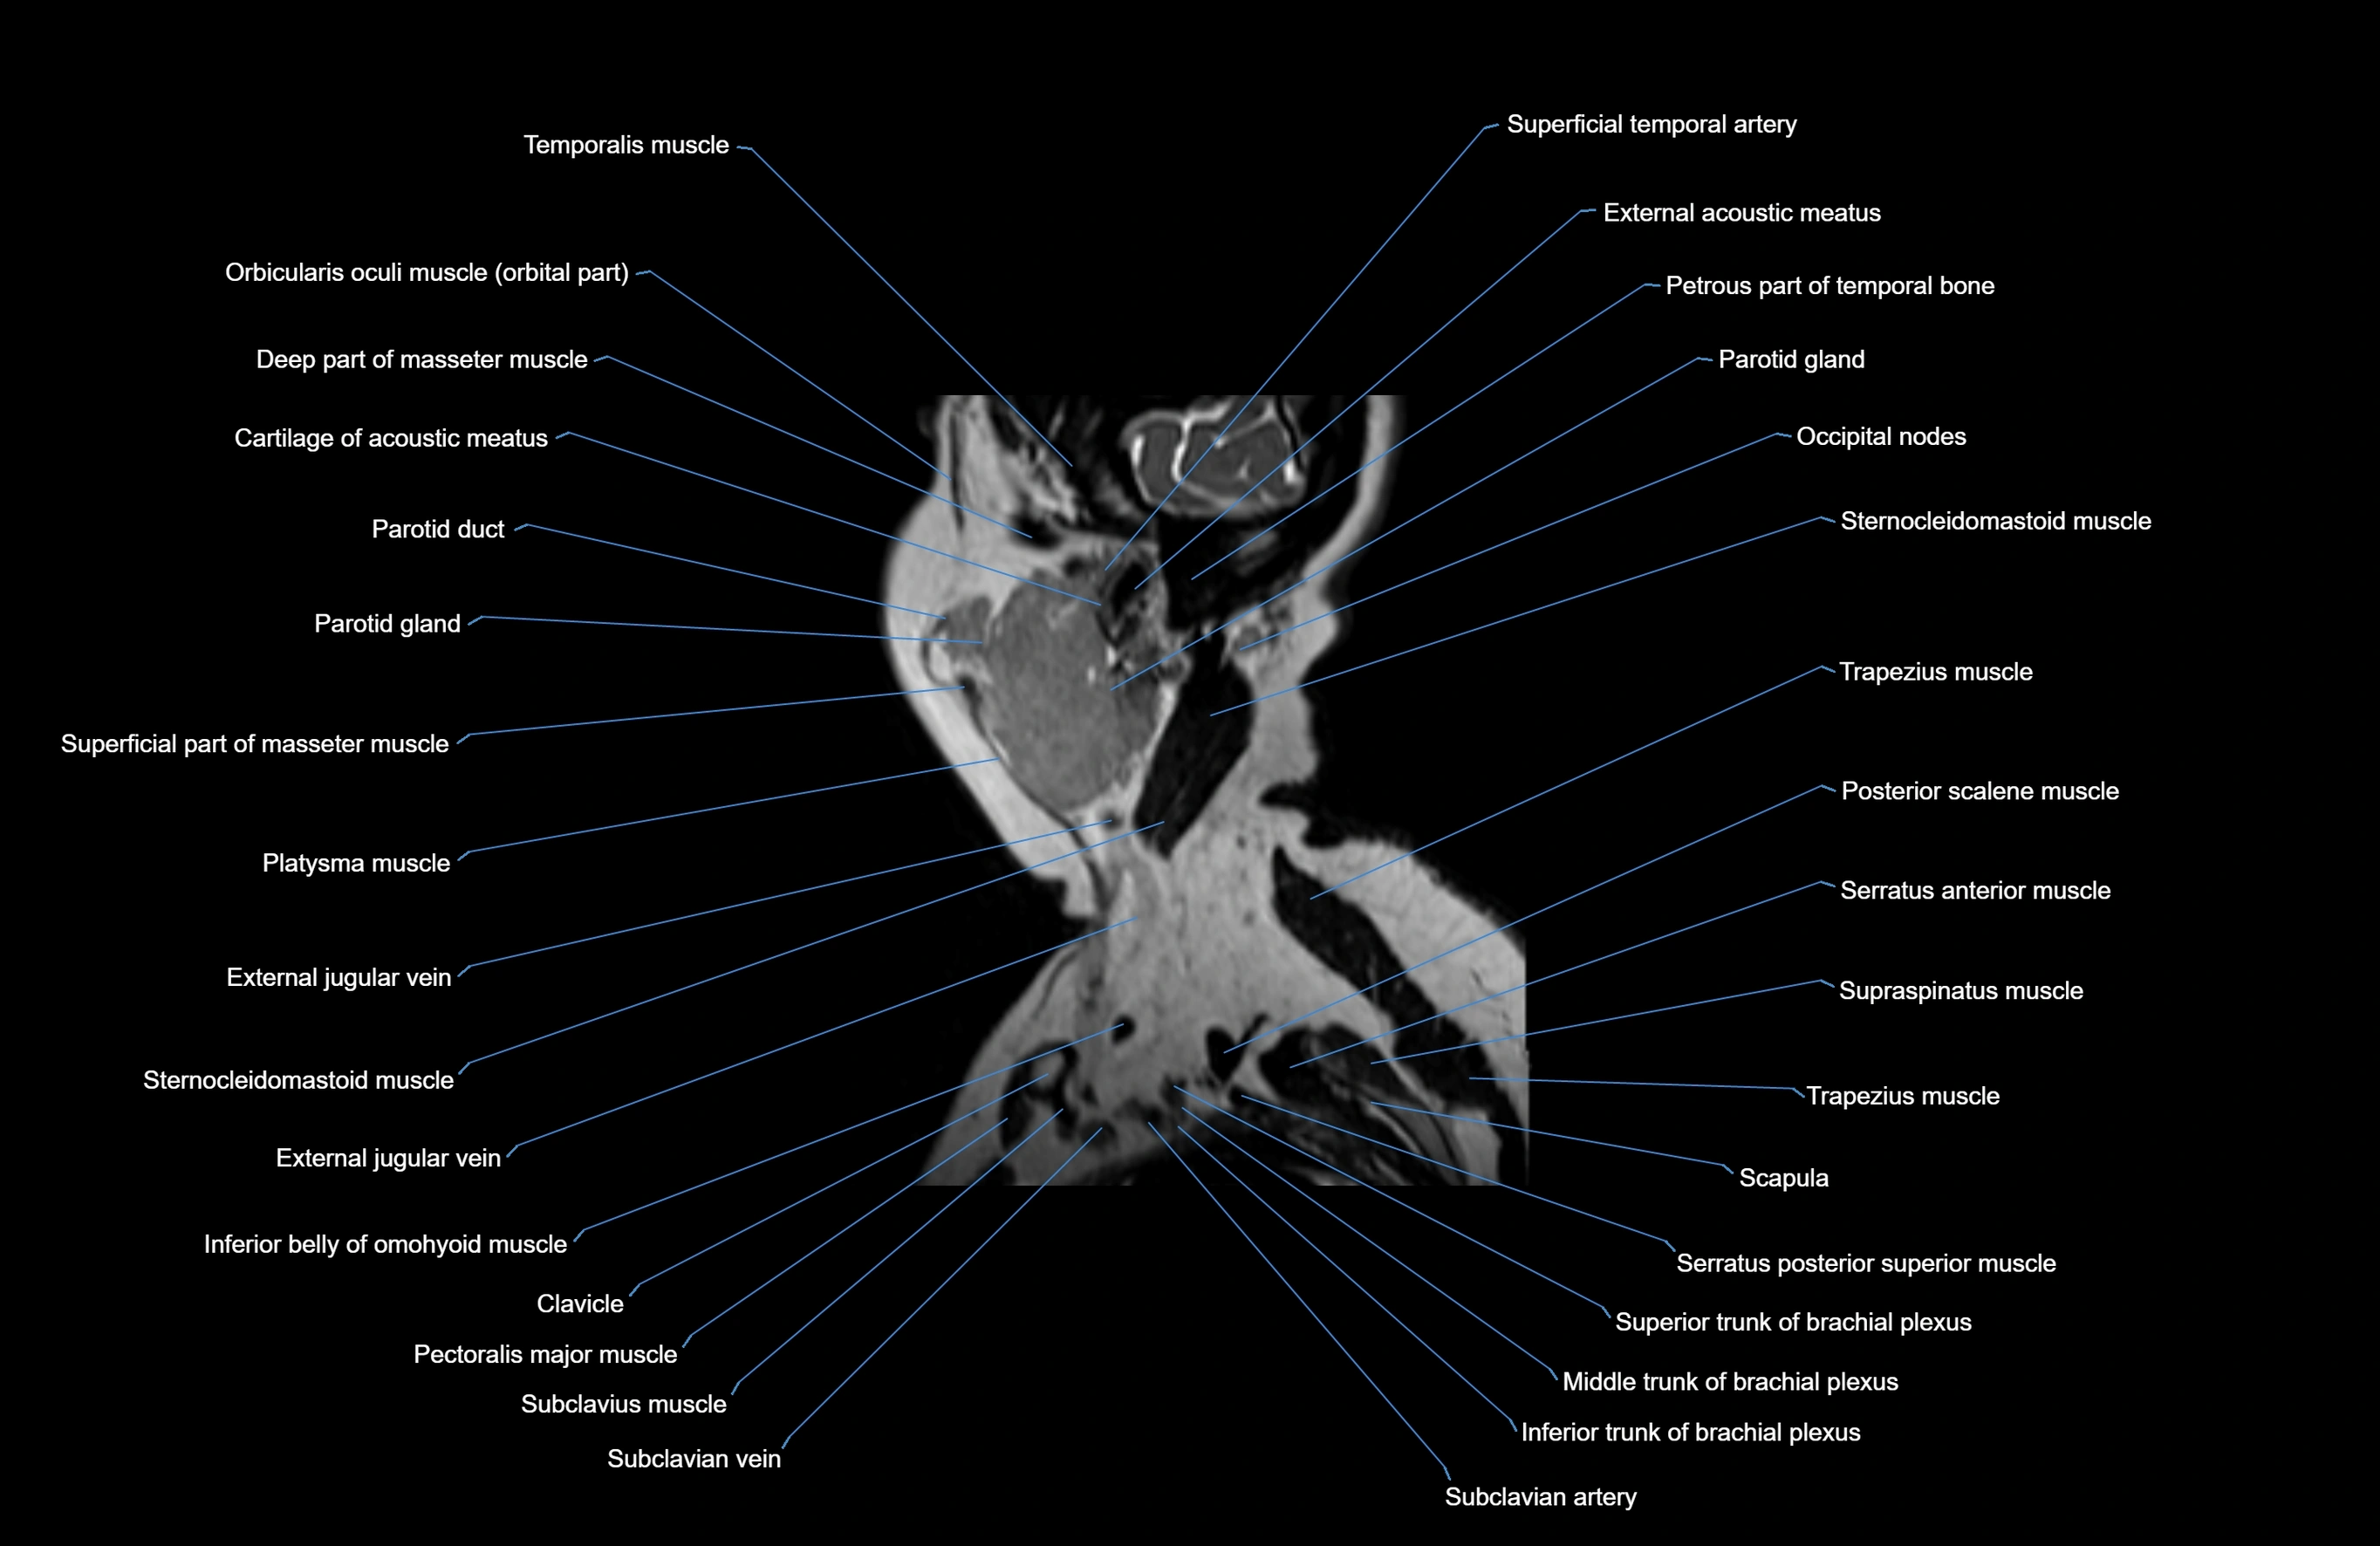

- Parotid gland

- Parotid duct

- External jugular vein

- Sternocleidomastoid muscle

- Trapezius muscle

- Scapula

- Supraspinatus muscle

- Serratus anterior muscle

- Subclavius muscle

- Pectoralis major muscle

- Subclavian artery

- Brachial plexus